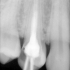

Domeną stomatologii zachowawczej jest zapobieganie oraz leczenie skutków najbardziej rozpowszechnionej choroby zębów, jaką jest próchnica. Z pojęciem próchnicy wiążą się następujące objawy: począwszy od nieestetycznych plam próchnicowych na zębach, poprzez ubytki twardych części zębów, które nie leczone mogą doprowadzić do podrażnienia i uszkodzenia wewnętrznej tkanki zęba - miazgi, co wiąże się z dolegliwościami bólowymi i wykluczeniem zęba z czynności żucia.

W skrajnych przypadkach nie leczona próchnica może doprowadzić do obumarcia zęba, co z kolei nie tylko pogarsza estetykę uśmiechu, ale może mieć wpływ na zdrowie całego organizmu - ukryte ognisko infekcji. Ostatecznym postępowaniem w leczeniu skutków próchnicy jest usunięcie zęba, co jest dużą stratą zważywszy na fakt, że nawet najdoskonalsze uzupełnienie nie zastąpi własnych, zdrowych zębów. Pacjenci zgłaszający się do nas spotkają się z fachową, rzetelną poradą i pomocą niezależnie od etapu rozwoju choroby próchnicowej dotykającej ich uzębienie.

- endodoncję - leczenie próchnicy powikłanej zapaleniem, obumarciem lub zgorzelą miazgi.